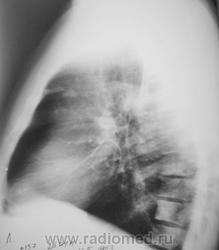

Сделали "томку".

Приложения:

1.p4260045a.jpg2.p4260046a.jpg3.p4260047a.jpg4.p4260048a.jpg5.p4260049a.jpg

Мысль всё о метастазах. Клинических проявлений нет никаких? В брюшной полости ничего не растет?

Мы тоже высказали мнение о наличии метастазов. У пациента установлен ( в области) рак предстательной железы, диагноз в ООД вверифицирован.